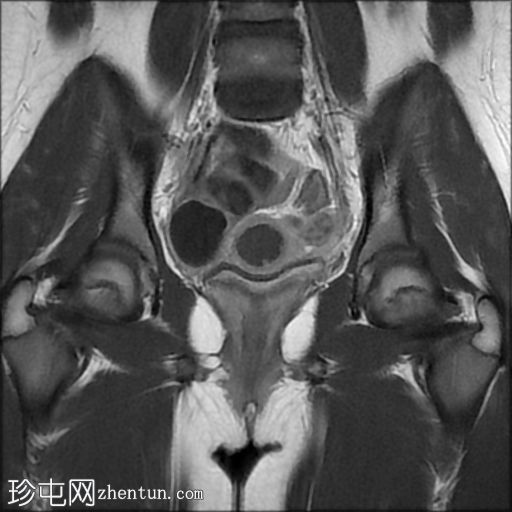

3.jpg

冠状面

T2

子宫体相对较小,发育良好。宫颈发育不全。

阴道整体不显影,远端可见一层细小的纤维组织,在轴向和矢状面T2加权序列上最为明显。

随后,子宫内膜和宫颈腔扩张,出现混合液体/血液降解信号(积血)。它诱发中至高T1信号,伴有依赖性低信号碎片,无病理性强化。

周围轻度盆腔积液,盆腔及附件脂肪平面模糊,信号相似,增强后强化明显。这些发现提示可能有渗漏液/血液积聚,并伴有腹膜反应。

右侧附件卵巢功能性囊肿。